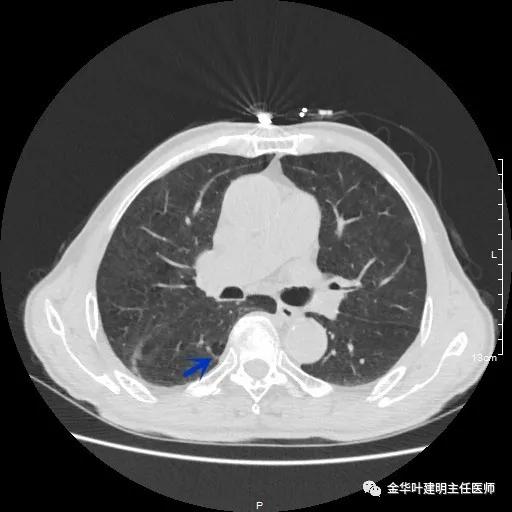

以上示右下叶病灶5。也是主病灶,是实性块状分叶的占位性病变,基本可以肯定是肺癌。单病灶看需下叶切除并清扫淋巴结。

以上示右下叶病灶6。同样是囊腔型病灶,但较前几个范围小,可囊壁同样为磨玻璃影,也是较为典型的囊腔型肺癌表现,单灶来看可下叶背段切除。